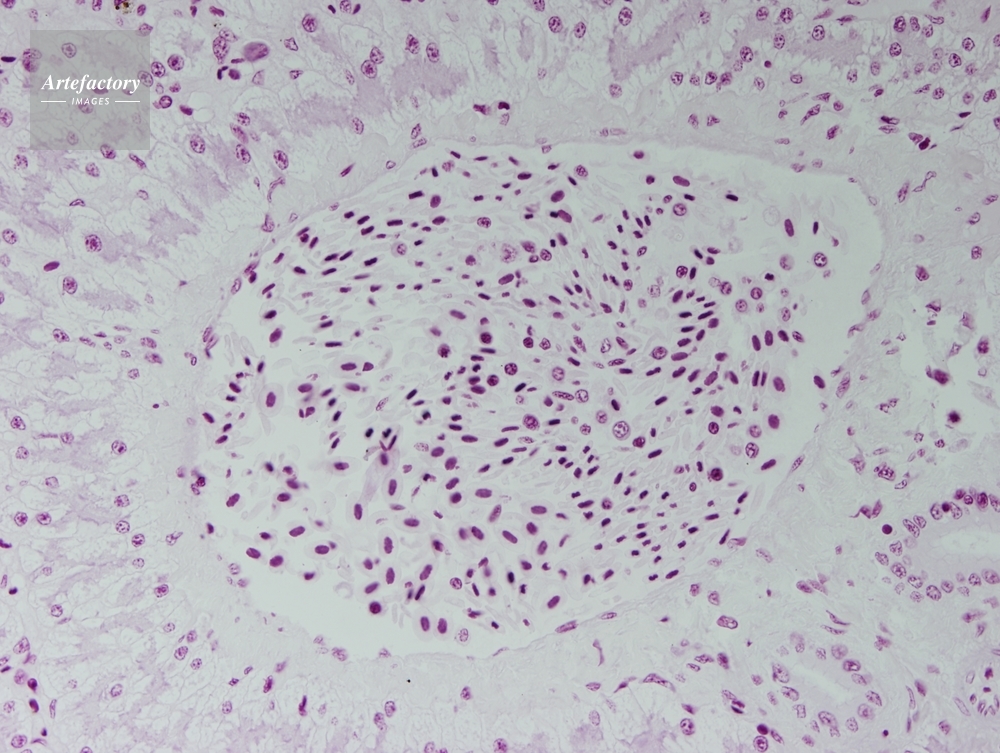

| 作品タイトル | カエル,肝臓 | モデルリリース | なし | |

| 作家 | OLYMPUS CORPORATION Technolab | プロパティリリース | なし | |

| ソース | ピクセル数 | 3455px × 2602px | ||

| 撮影地 | 印刷サイズ | 20.3cm × 15.3cm | ||

| 撮影年月日 | 2007/6/27 | データサイズ | 4.4MByte | |